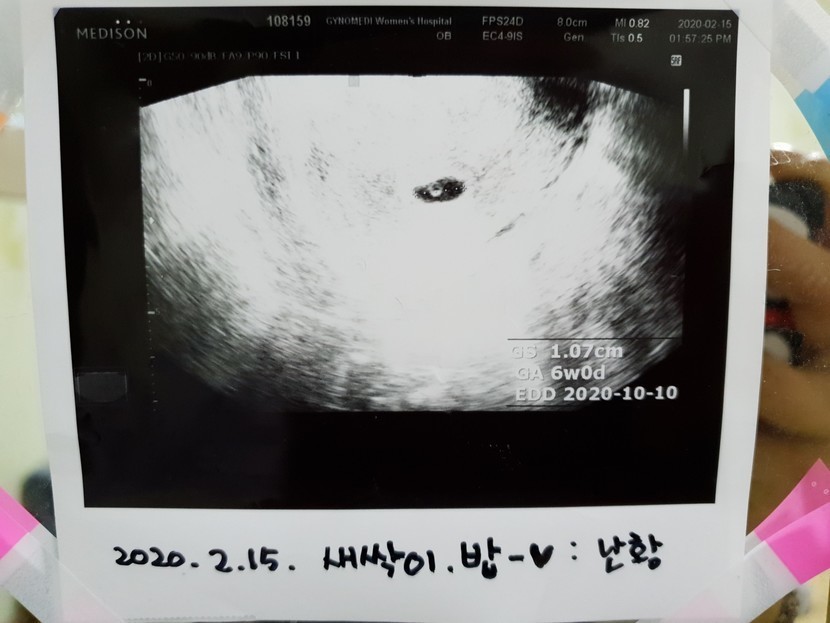

일주일뒤에 오래서 갔더니

예전에는 심장뛰는거 봐야 임신확인서를 주는데

요새는 아기집만 초음파로 보일시

임신확인서를 끈어주네요ㅎㅎ

그리고 2주뒤에오면 새싹이 심장뛰는거

볼수있다해서 기다리다가

초음파보니 출혈은안보인데요..

난황이보이네요

조금찌그러졋다고는하는데ㅜㅜ

아기집.난황 근데 초음파상으로는

아무이상없고